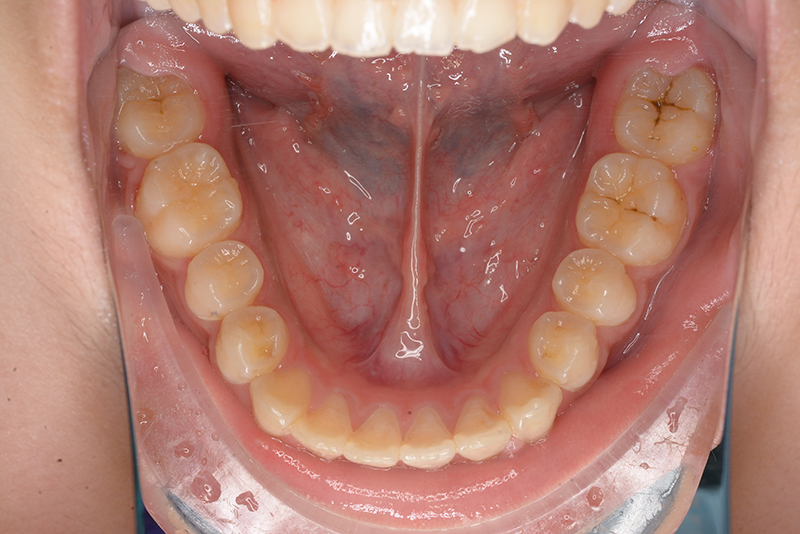

動的治療終了時

FP・IOP

批評・予后 上顎前歯舌側移動により上口唇形態は改善したこと、また動的治療中の下顎骨、特に下顎枝の成長が認められ下顔面高さは高くなったことが相俟って良好なプロファイルは得られたと思う。咬合の緊密化や歯根のパラレリングは行えたように思う。今後は第三大臼歯の萌出方向に注意を払い、頃合いを見計らって抜歯を検討している。